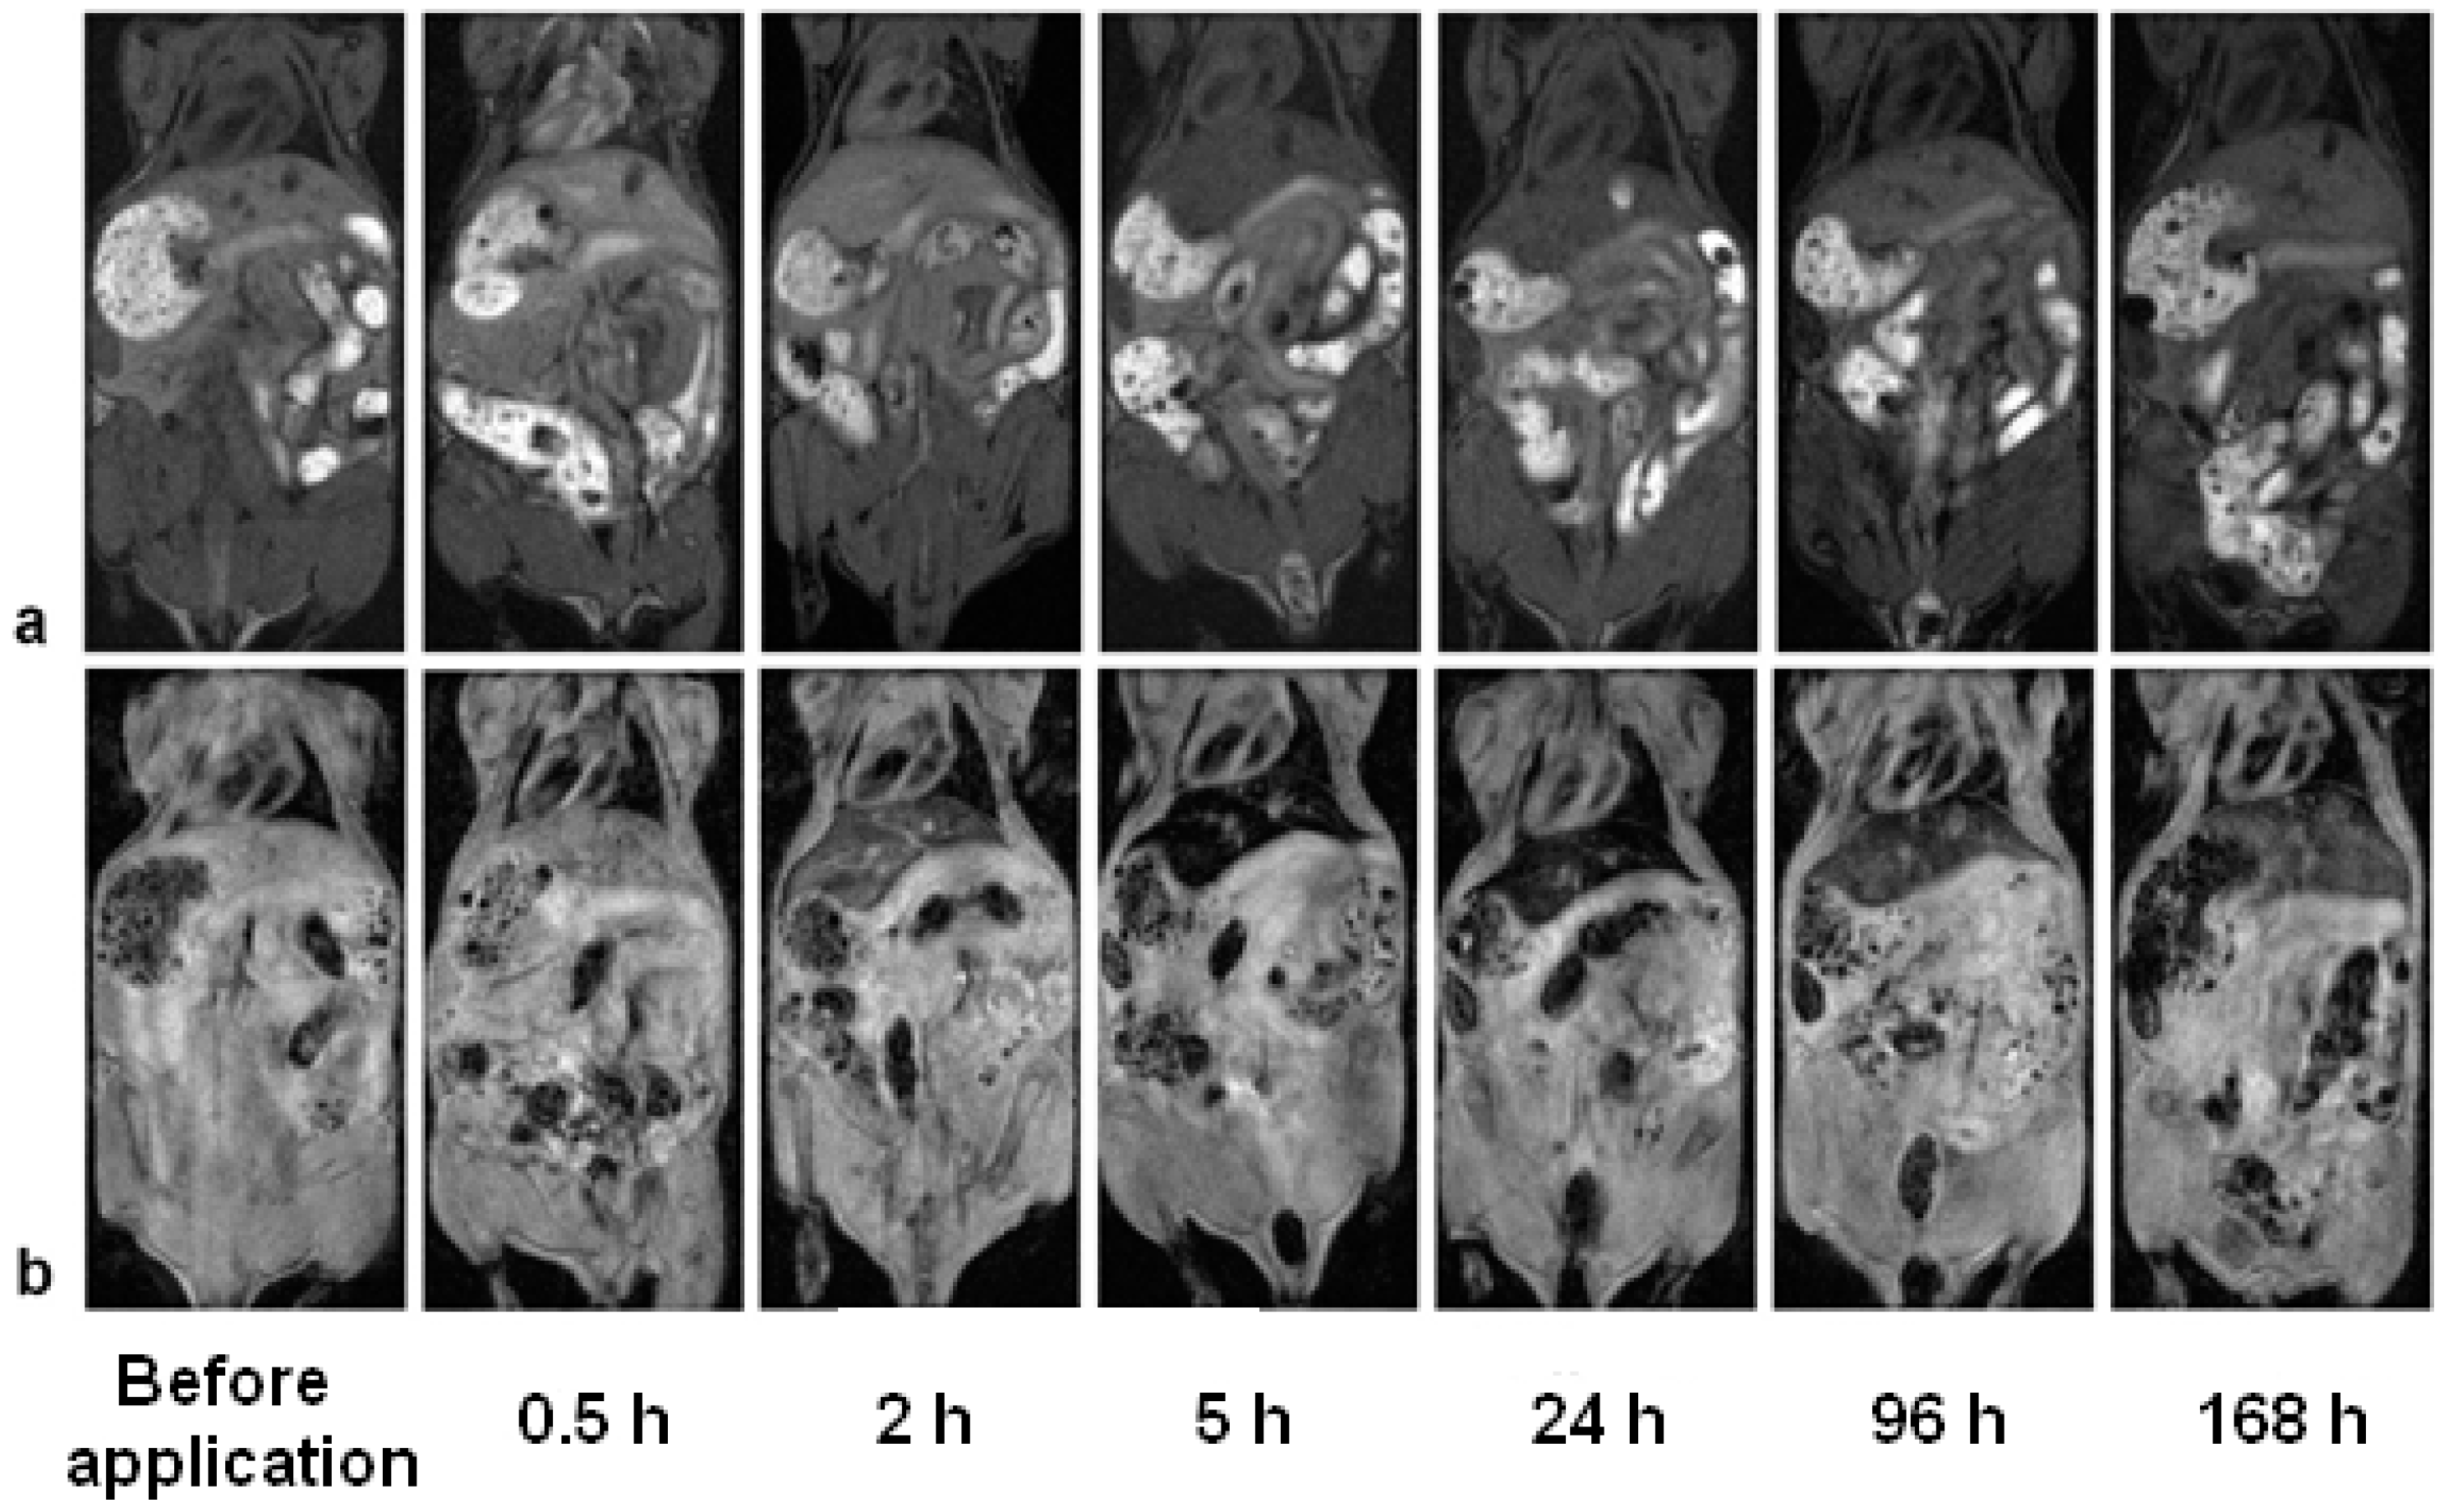

3.6. In Vivo MR Imaging of Gd(Tb)F3:Tb3+(Gd3+),Yb3+,Nd3+@P(DMA-AGME)-Ale Nanoparticles